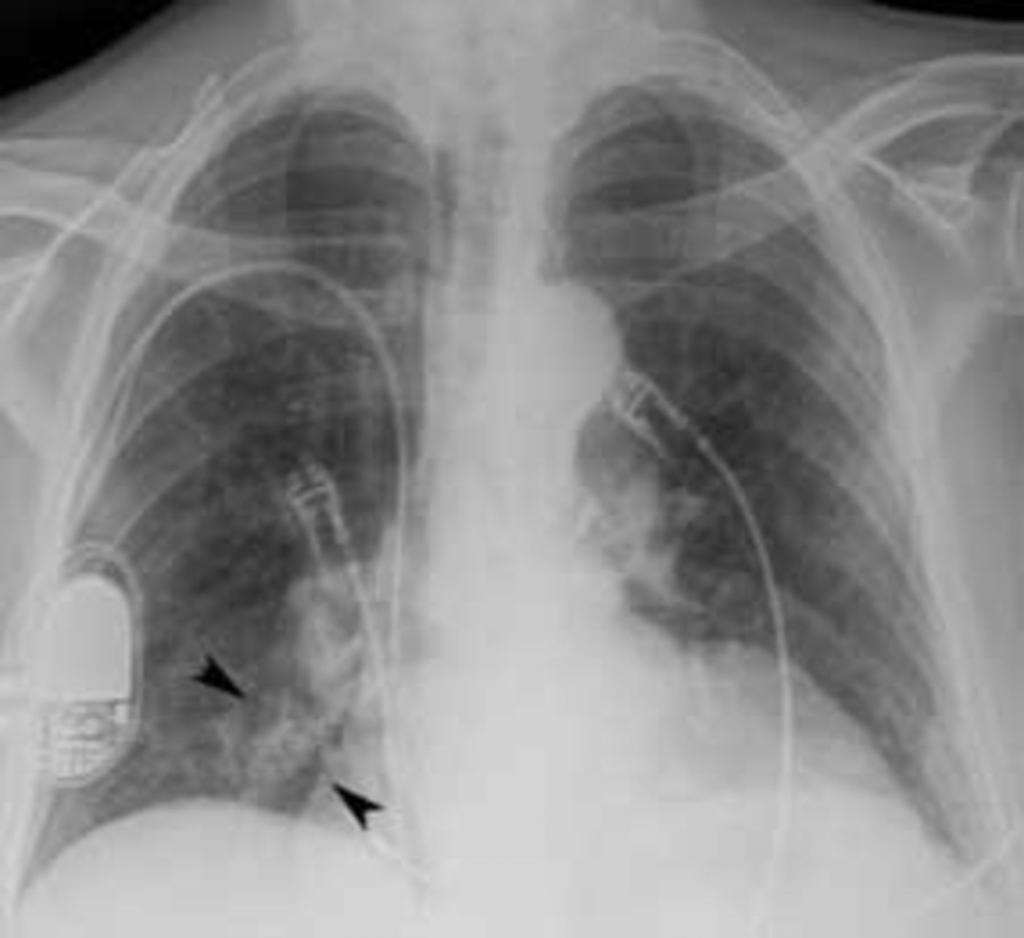

При пневмонии, на рентгеновском снимке легких, видны следующие признаки:

- в разных частях органа находятся очаги затемнения, имеющие неровные контуры и размер 3-12 мм;

- различаются тени по внешнему виду (овальные, кольцевидные, круглые), интенсивности цвета – чем темнее будет пятно, тем сильнее патологический процесс;

- если поражены лимфатические узлы и нарушено кровоснабжение органа, может быть заметно изменение корней лёгких, если поражена плевра – видны нарушения в рисунке куполов диафрагмы.

На рентгеновском снимке пневмония выглядит следующим образом: